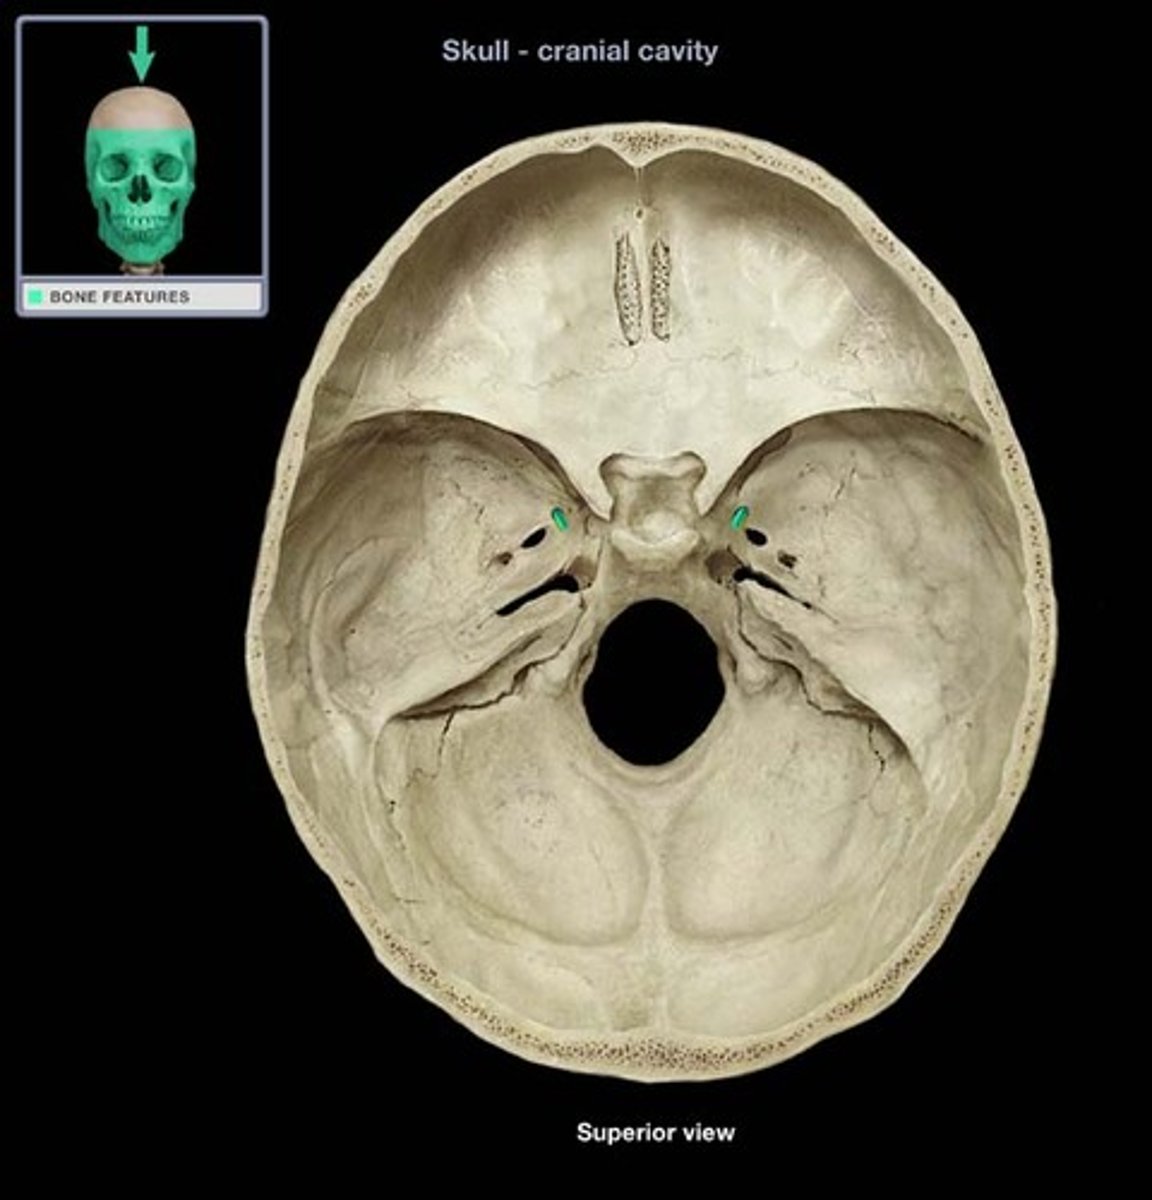

Foramen Magnum

The hole in the base of the skull through which the spinal cord passes

Hypoglossal Canal

Foramen in the occipital bone of the skull through which the hypoglossal nerve traverses

Foramen Lacerum

A triangular hole in the base of the skull located between the sphenoid, apex of petrous temporal and basilar part of occipital

Jugular Foramen

CN IX, X, XI, superior bulb of internal jugular, inferior petrosal and sigmoid sunuses, meningeal branches of ascending pharyngeal and occipital arteries pass through

Occipital Condyles

Rounded projections lateral to the foramen magnum that articulate with the first cervical vertebra (atlas)

Foramen Rotundum

Located at the base of the greater wing of the sphenoid, inferior to the superior orbital fissure. It provides a connection between the middle cranial fossa and the pterygopalatine fossa. The maxillary nerve (branch of the trigeminal nerve, CN V) passes through this foramen.

Foramen Spinosum

The middle meningeal artery, middle meningeal vein, and the meningeal branch of the mandibular nerve pass through the foramen.

Foramen Ovale

An oval shaped opening in the middle cranial fossa located at the posterior base of the greater wing of the sphenoid bone. It transmits the mandibular division of the trigeminal nerve (CN V3) and the accessory meningeal artery.

Internal Acoustic Meatus

A passage for CN VIII from the inner ear to the brain

Carotid Canal

The passageway in the temporal bone through which the internal carotid artery enters the middle cranial fossa from the neck

Cribriform Plate

Superior surface of the ethmoid; perforated by a foramina which allows passage of the olfactory nerves, which provide sense of smell

Crista Galli

A thick, midline, smooth triangular process arising from the superior surface of the ethmoid bone, projecting into the anterior cranial fossa. Attaches to fall cerebri.